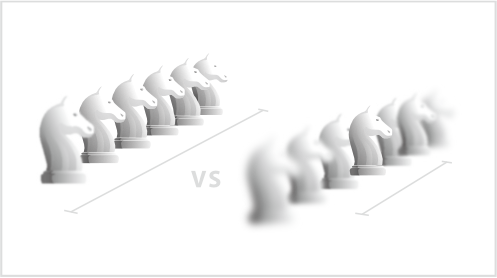

3-200mm Depth of Field

Focus remains clear while switching between multiple operating scenes.